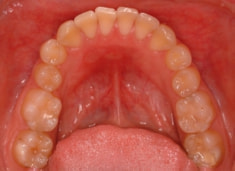

治療後(1年9ヶ月後)